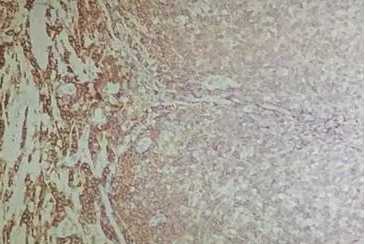

一、固定不充分

10%中性福爾馬林是目前應(yīng)用最廣泛且效果較好的固定方式。組織塊太大,或固定時(shí)間太短,都會(huì)導(dǎo)致固定不充分。一般8-24h為宜,具體還需要經(jīng)過實(shí)際操作摸索確定。如圖1的這種情況,可適當(dāng)延長固定時(shí)間到48h。

圖1 固定不充分